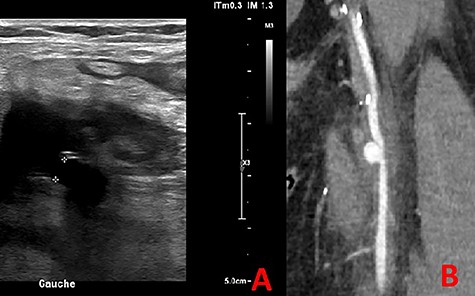

At 3-month follow-up, he presented to emergency room with a popliteal and left calf pain that has been worsening for 2 days. The echo Doppler revealed a popliteal and femoral deep vein thrombosis, and a left SFA PSA (15 × 18 mm) circulating with a 5-mm collar (Fig. 6A).

The CTA confirmed a PSA measuring 13 mm in diameter (Fig. 6B).